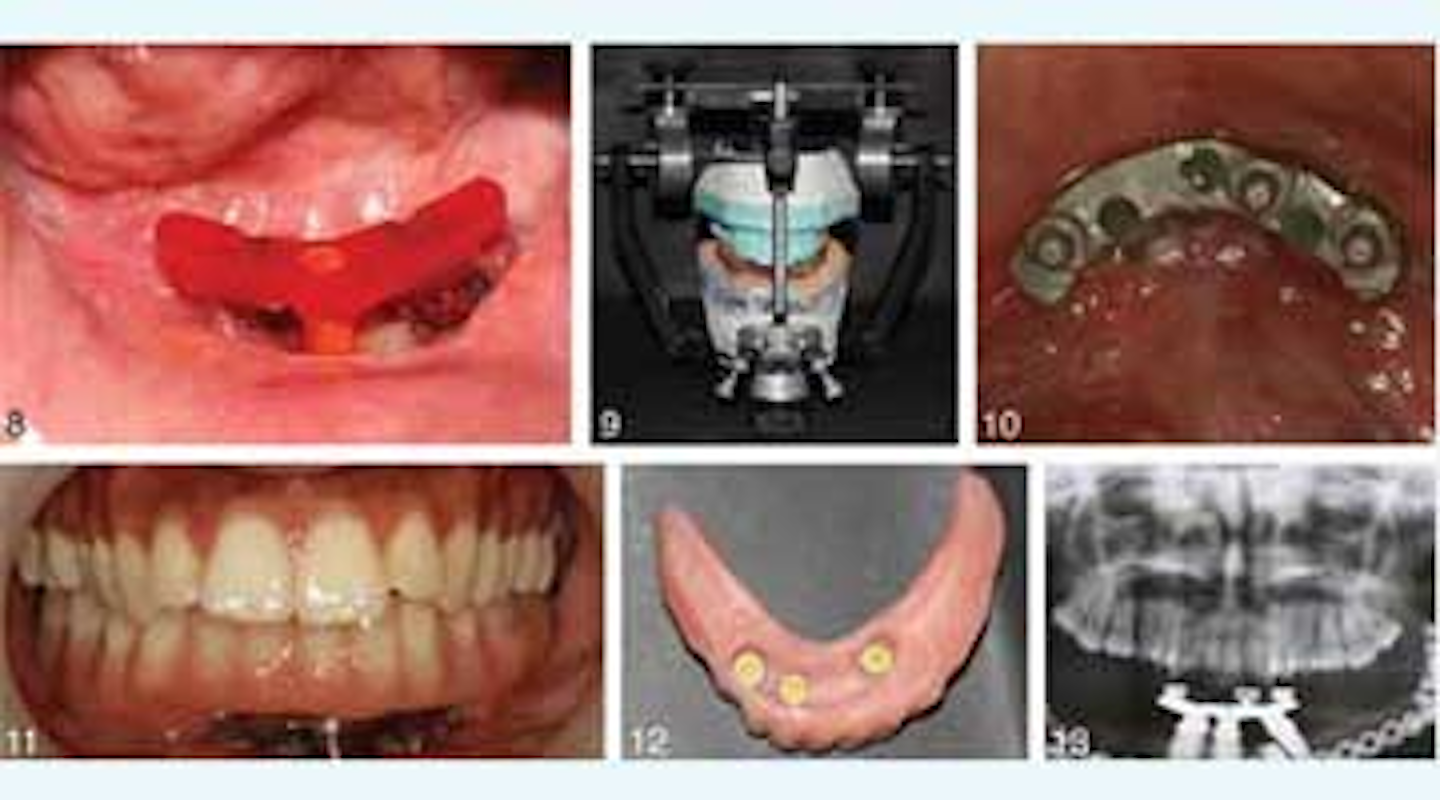

Dental implants help leg bone successfully replace jawbone PerioImplant Advisory How To Build Bone In Jaw Even so, there are many things you can do. learn how to regrow jaw bone naturally using effective techniques and remedies. How to detect, prevent, and treat it. there are various exercises to help sharpen your jawline and bring out your inner macho. Discover natural methods for promoting jaw bone regeneration. Did you know that bone loss in. How To Build Bone In Jaw.